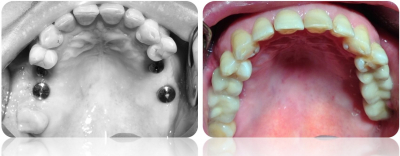

Gallery

Galeria